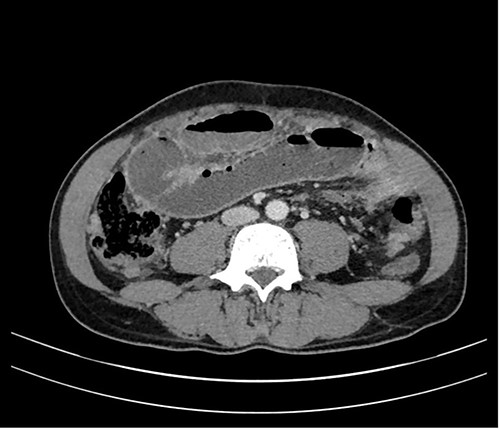

In a previous healthy 41-year-old male with a 3-month history of abdominal pain, fever, fatigue, night sweats and weight loss of 5 kg, a computed tomography (CT) of the abdomen revealed a mechanical ileus due to suspected distinct peritoneal carcinomatosis in the entire abdomen of an unknown primary (Fig. 1).

A 53-year-old female of Indian origin, resident in Switzerland for 20 years, presented with diffuse abdominal pain, nausea and meteorism in the primary care consultation. After an initial workup with blood tests and ultrasound (US), a CT of the abdomen was performed (Fig. 3), which revealed enlarged, central necrotic lymph nodes adjacent to the common bile duct (CBD) and the pancreatic head. The enlarged lymph nodes caused an obstruction of the CBD. The patient was referred to our institution for further diagnostic tests.